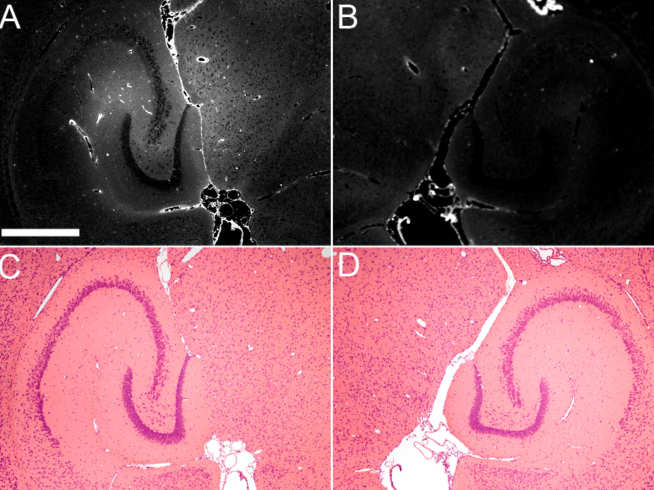

Current Alzheimer’s Disease (AD) drugs treat symptoms, but not the underlying disease process. Despite the availability of neurologically potent drugs (eg, inhibitors, antibodies), cerebral capillaries (ie, blood-brain barrier) block their entry into the brain.

The student will design, construct, and characterise a non-invasive ultrasound-based technology that drives systemically administered microbubbles into volumetric oscillations. This technology exerts mechanical stress from within the capillaries to increase permeability and allow drugs safe passage into the brain. The student will then use this technology to deliver drugs in transgenic AD mice, reduce AD pathology, and improve cognitive function.